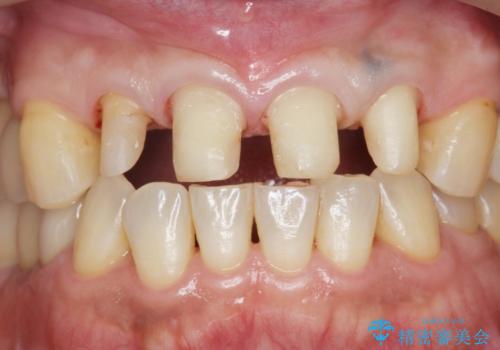

- 前歯の虫歯に気付きながらも放置し、一念発起し治療を希望され来院されました。

虫歯のマイクロスコープによる丁寧な除去、根管治療、深い虫歯に対する挺出(エクストリュージョン)および歯周外科を行ったのち精度の高いセラミッククラウン製作治療を計画します。

虫歯の放置により、根管治療や深い虫歯に対する処置が必要になりましたが丁寧に一つづつ処置を行ったことで抜歯をすることなく歯を残すことができました。

セラミッククラウンの製作をする前に、歯内・歯周環境の整備は非常に大切です。